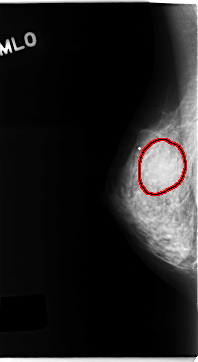

C_0154_1.RIGHT_MLO

RIGHT_MLO LINES 4704 PIXELS_PER_LINE 2568 BITS_PER_PIXEL 12 RESOLUTION 50 OVERLAY

FILE: C_0154_1.RIGHT_MLO.OVERLAY

TOTAL_ABNORMALITIES 1

ABNORMALITY 1

LESION_TYPE MASS SHAPE ROUND MARGINS ILL_DEFINED

ASSESSMENT 4

SUBTLETY 3

PATHOLOGY MALIGNANT

TOTAL_OUTLINES 1

BOUNDARY